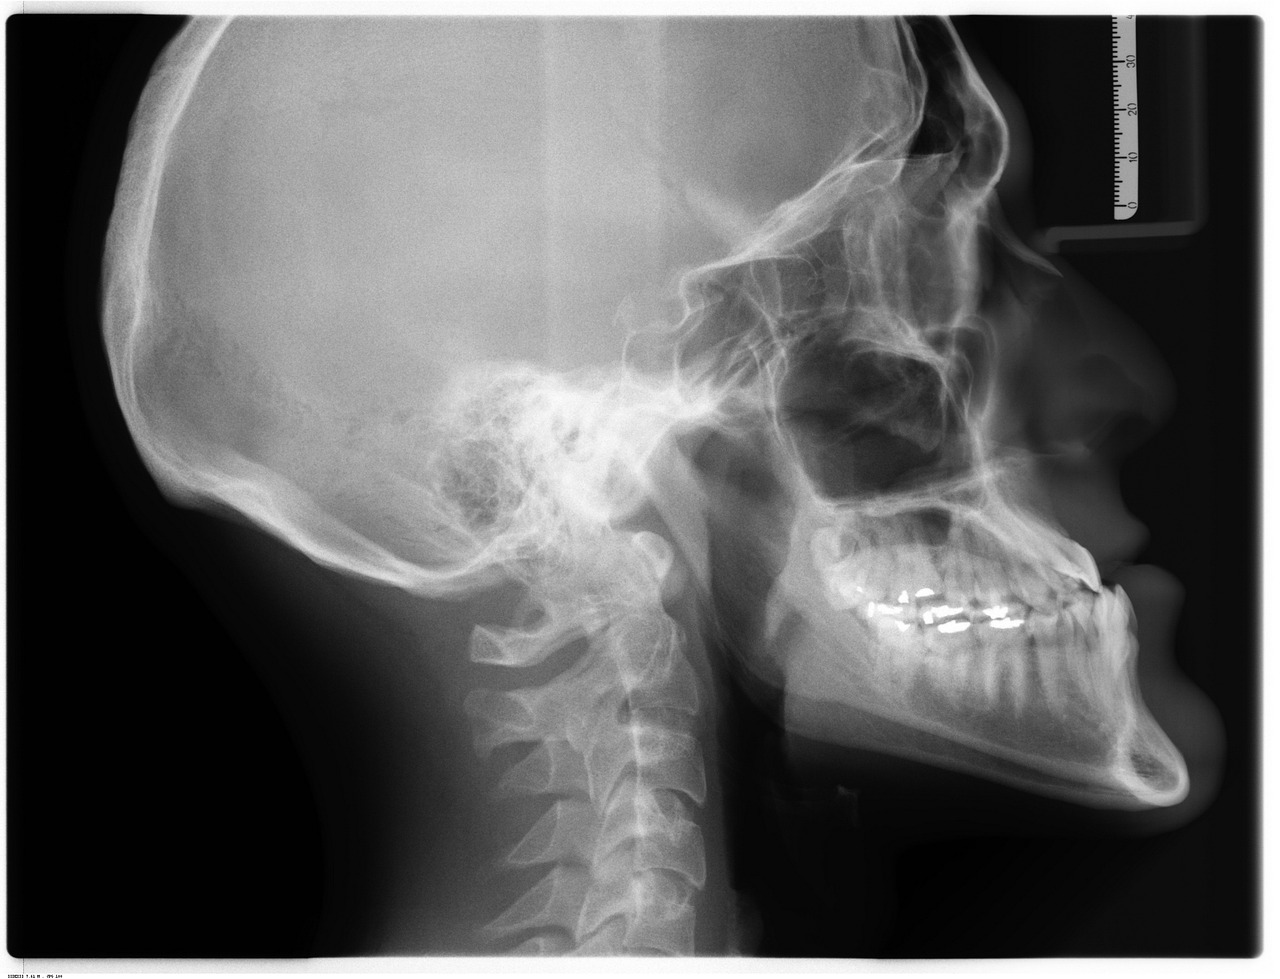

Prześwietlenie barku, czyli badanie RTG, to jedna z najczęściej stosowanych metod obrazowania w diagnostyce schorzeń i urazów stawu barkowego. W trakcie procedury wykorzystywane jest promieniowanie rentgenowskie, które pozwala uzyskać szczegółowe obrazy struktur kostnych tej okolicy. Badanie jest całkowicie bezbolesne, trwa zaledwie kilka do kilkunastu minut i nie wymaga specjalnego przygotowania ze strony pacjenta. Dzięki swojej dostępności oraz szybkości wykonania, RTG stanowi podstawowe narzędzie w ocenie urazów czy przewlekłych dolegliwości barku.

W zależności od wskazań klinicznych, zdjęcia wykonywane są w różnych projekcjach – najczęściej stosuje się projekcję AP (przednio-tylną), osiową, a także tzw. projekcję Y lub transtorakalną (boczną przez klatkę piersiową). Pozwala to na precyzyjną ocenę takich struktur jak kość ramienna, łopatka, obojczyk oraz stawy: barkowy, barkowo-obojczykowy i obojczykowo-mostkowy. Nowoczesne pracownie radiologiczne oferują cyfrowe przesyłanie wyników – obrazy trafiają bezpośrednio do systemu opisowego lekarza radiologa, a pacjent otrzymuje je zazwyczaj na nośniku elektronicznym (CD lub DVD). Takie rozwiązanie umożliwia szybkie przekazanie wyników zarówno do lekarza prowadzącego, jak i do innych specjalistów w razie potrzeby dalszej diagnostyki lub konsultacji.

Co oznaczają wyniki RTG barku? Najczęstsze pojęcia w opisach badań

Interpretacja wyniku prześwietlenia barku opiera się na analizie charakterystycznych zmian widocznych w strukturach kostno-stawowych. W opisach radiologicznych często pojawiają się określenia takie jak zmiany zwyrodnieniowe, które mogą być opisane jako początkowe, stopniowe lub zaawansowane. Oznaczają one procesy degeneracyjne prowadzące do utraty chrząstki stawowej i powstawania osteofitów, co przekłada się na ból oraz ograniczenie ruchomości. Innym często spotykanym pojęciem jest PHS (periarthritis humeroscapularis), czyli zespół bolesnego barku – termin ten obejmuje grupę objawów związanych z zapaleniem, uszkodzeniem ścięgien lub kaletek okołostawowych, a także zmianami w obrębie stawu barkowo-obojczykowego.

Wynik badania RTG może również zawierać informacje o cechach zapalenia stawu, takich jak obrzęk tkanek miękkich czy zwężenie szpary stawowej, a także o obecności uszkodzeń ścięgien lub innych struktur miękkotkankowych. Radiolog ocenia także stan stawu barkowo-obojczykowego – jego deformacje, zwapnienia czy ślady przebytych urazów mogą mieć istotne znaczenie dla dalszego postępowania terapeutycznego. W zależności od wykrytych nieprawidłowości lekarz prowadzący może zdecydować o konieczności rozszerzenia diagnostyki (np. o rezonans magnetyczny) lub wdrożeniu odpowiedniego leczenia zachowawczego bądź operacyjnego.